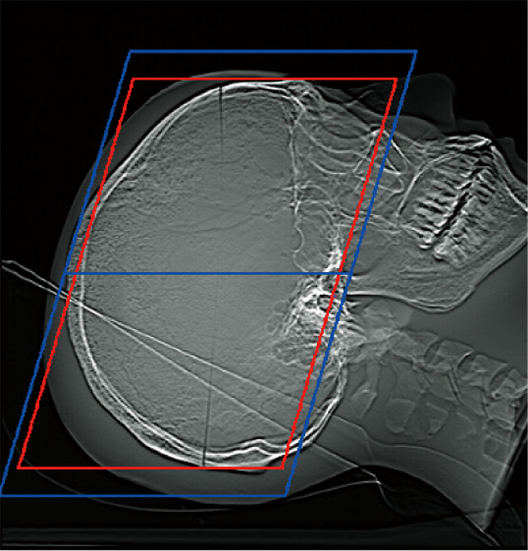

The scan range can be automatically set by the scanogram image. It is expected to improve reproducibility of scan position and efficiency of examinations, contributing to time reduction.

The scan range can be customized according to the operation of the facility since the margin of the scan range can be set in advance. The operator can also check and adjust the automatically calculated scan range.*7

OM Line

SM Line Head

RB Line

Chest

Red: Position set automatically

Blue: Position set automatically + set margin